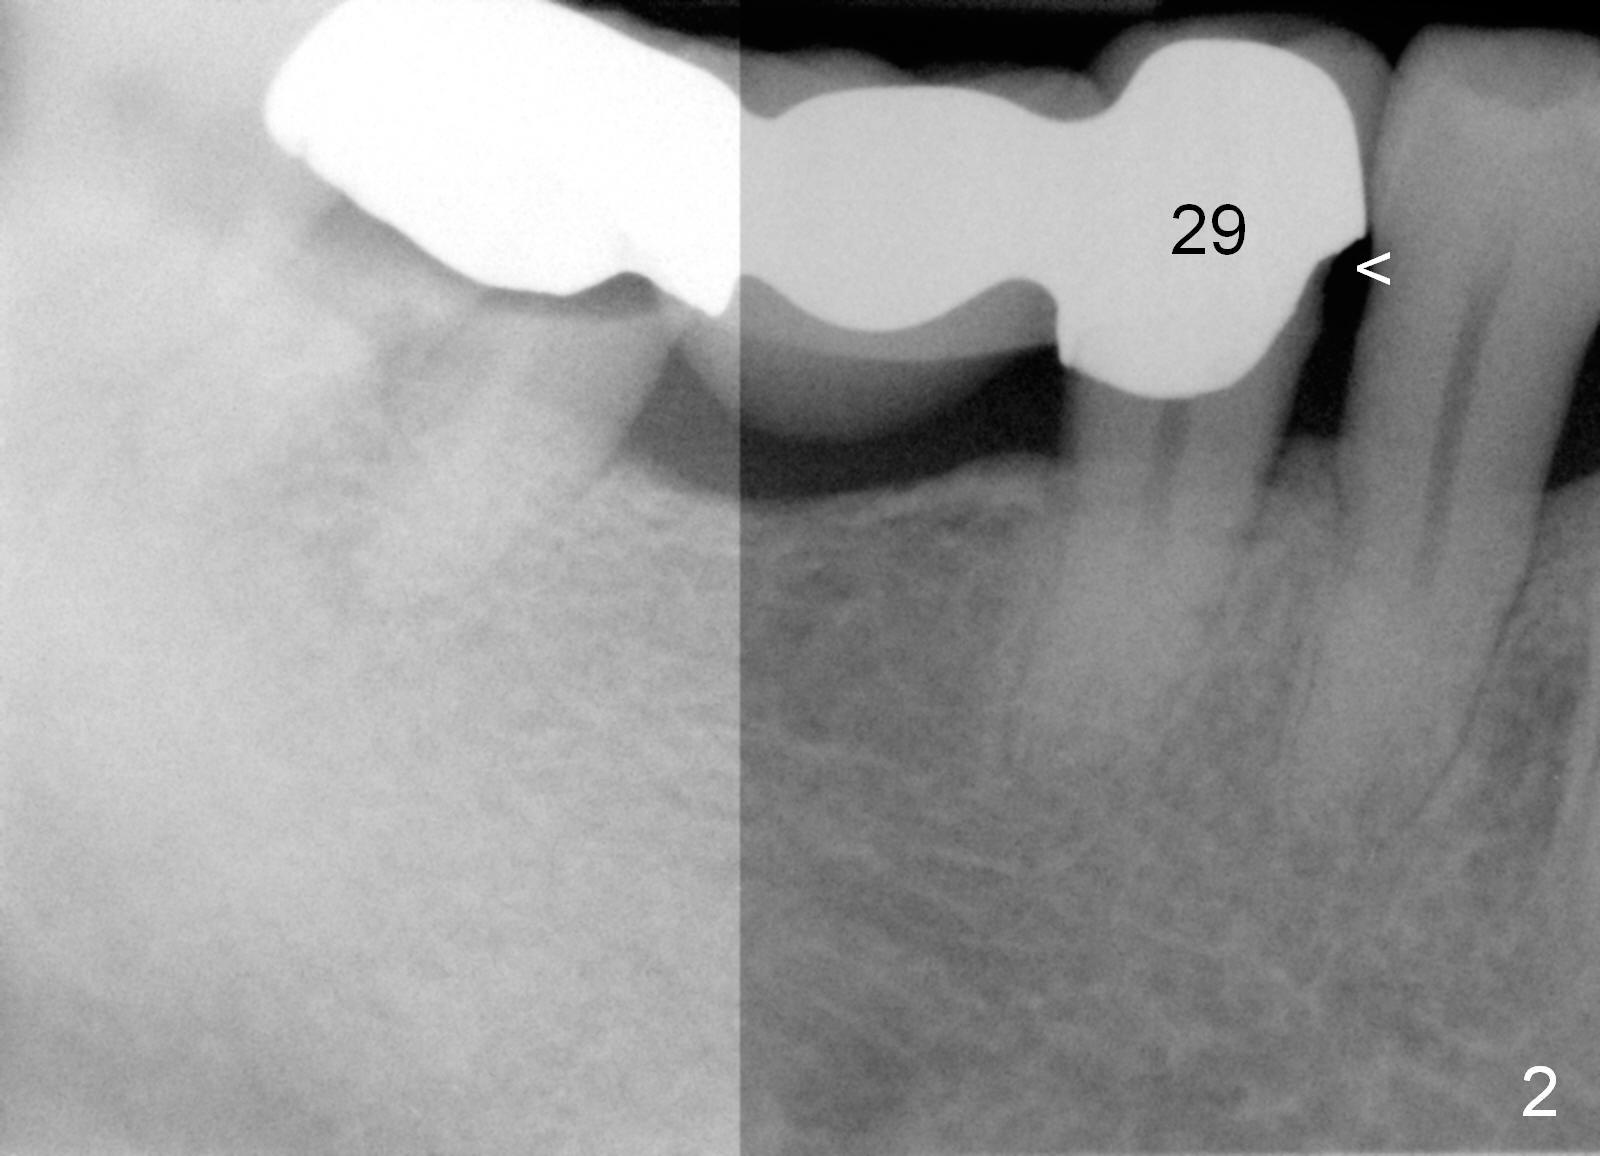

A 47-year-old man works in Africa. While he is visiting his family at Atlanta, he has toothache in the lower right. Examination reveals secondary caries under #31 retainer (Fig.1) and mesial open margin of #28 retainer (Fig.2). Surgery is scheduled next day.

Before sectioning between #29 and 30 (Fig.4 dashed line), take Alginate impression for the lower right quadrant to fabricate a surgical stent. Two implants are to be placed at the sites of #30 (5x14 mm) and 31 (6x14 mm) (Fig.3,4).